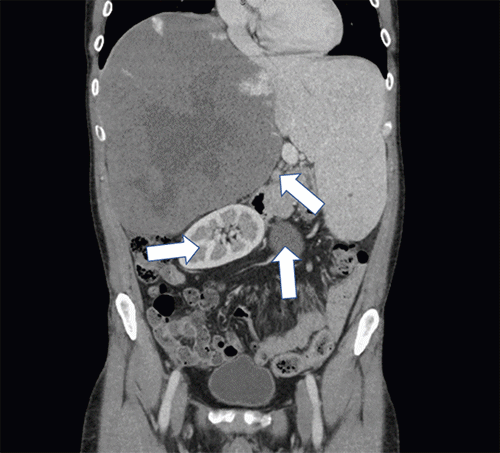

In the months preceding surgery, the patient developed progressive symptoms, including shortness of breath, abdominal fullness, early satiety, and worsening varicose veins. Repeat imaging revealed significant growth of the hemangioma (21.8 × 21.8 × 25.2 cm). The mass exerted a substantial compressive effect on the liver parenchyma, displacing surrounding organs like the gallbladder, stomach, duodenum, and pancreas inferiorly (Figure 1).

Figure 1. Coronal View of Triple-Phase CT Abdomen/Pelvis with Contrast. Published with Permission

Hemangioma: Characteristic “centripetal fill-in” pattern is evident in the portal venous phase (arrow). Mass effect: Note the inferior displacement of the right kidney and leftward displacement of the gallbladder and inferior vena cava.